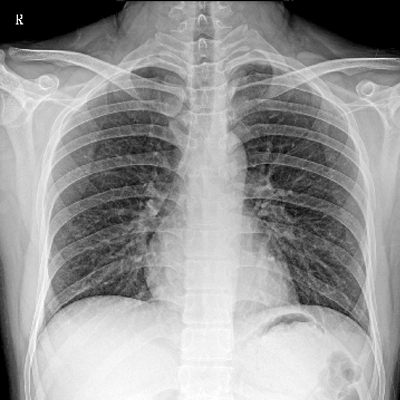

輕量化設(shè)計(jì) 小巧靈活 PLX5100

用于影像科、急診室、病房、ICU、手術(shù)室等多場(chǎng)景應(yīng)用。

● 數(shù)字化無線平板成像,操作簡(jiǎn)便,成像質(zhì)量高